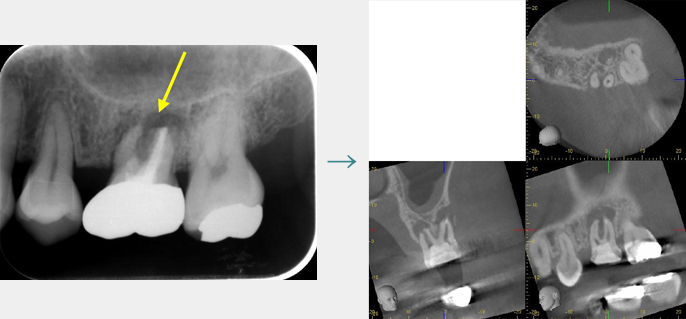

CTによる診断

CT画像ではあらゆる方向から確認することができるため、二次元のレントゲンより情報が多く、より確実な診断を行うことが可能です。

歯周病の進行によって溶けてしまった骨を、歯周再生療法によって回復しています。

こちらはCTによる3次元的な画像です。

歯周病による骨の溶け具合は、歯の形態や位置によって様々です。

歯の裏側だけに限局していることもあれば、歯の全周で進行することもあります。

歯周病の診断には、3次元的に骨の形態が把握できるCT撮影が有効です。

CT画像から、歯周病の病態・進行程度を診断し、治療計画を立案します。

(ただし、再生療法は骨の溶け方によっては適応が困難な場合もあります。)